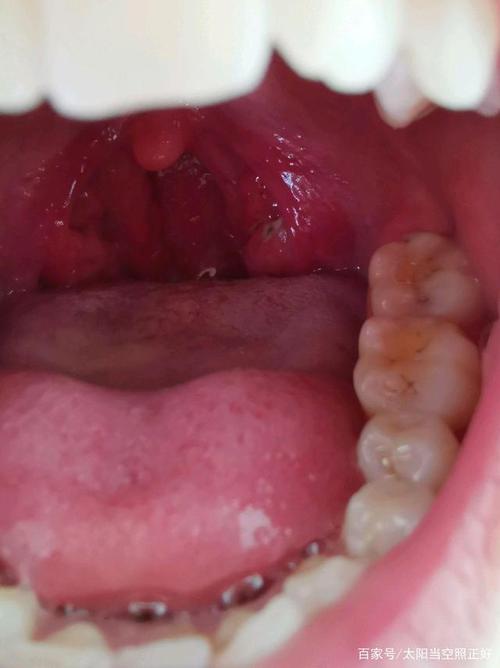

扁桃体窝白色东西图片

扁桃体窝白色东西图片,扁桃体白斑图片

扁桃体是一堆扁卵圆形的淋巴器官,它藏匿于扁桃体窝内,腭咽弓和

扁桃体窝白色东西

扁桃体窝图片